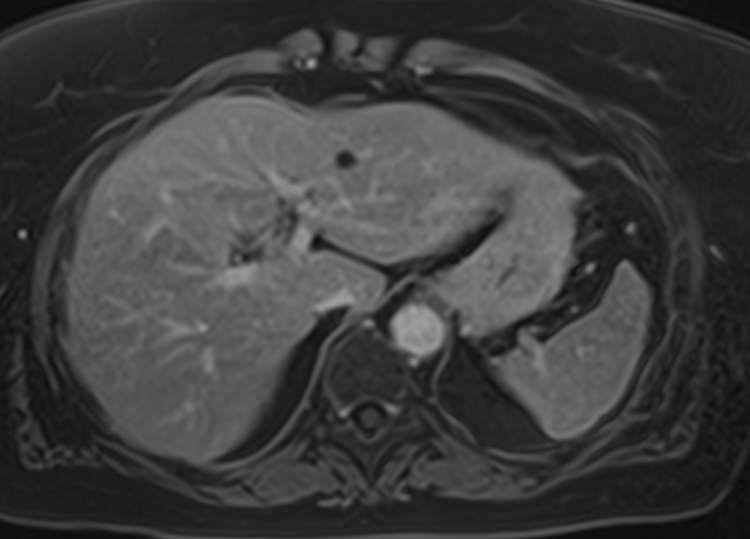

Для расширения возможностей диагностики, при необходимости уточнения характера патологических изменений, в случае подозрения на опухолевый процесс, дополнительно применяется контрастное усиление.

Для этого в вену вводится контрастный препарат, содержащий металл гадолиний (Магневист, Гадовист, Омнискан и др). Степень и характер накопления контрастного препарата в органах и тканях позволяет различать патологические процессы. Это дает возможность, в частности, диагностировать патологические очаги минимальных размеров, что бывает особенно важно в ранней диагностике опухолей.